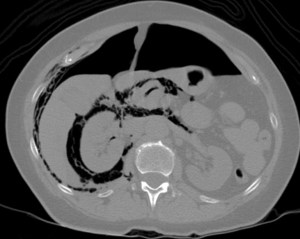

CASO 1: Paciente de 58 años que se realiza TC de abdomen tras historia de dolor abdominal y hematuria microscópica. Refiere pérdida de peso en las últimas semanas.

Estamos ante una afectación bilateral del espacio perirrenal, más evidente en el lado derecho, por masas de densidad de partes blandas en un paciente con numerosas adenopatías retroperitoneales. Estaría indicado realizar una biopsia, ya que el diagnóstico principal orienta hacia un síndrome linfoproliferativo, espcialmente linfoma no Hodgkin tipo B.